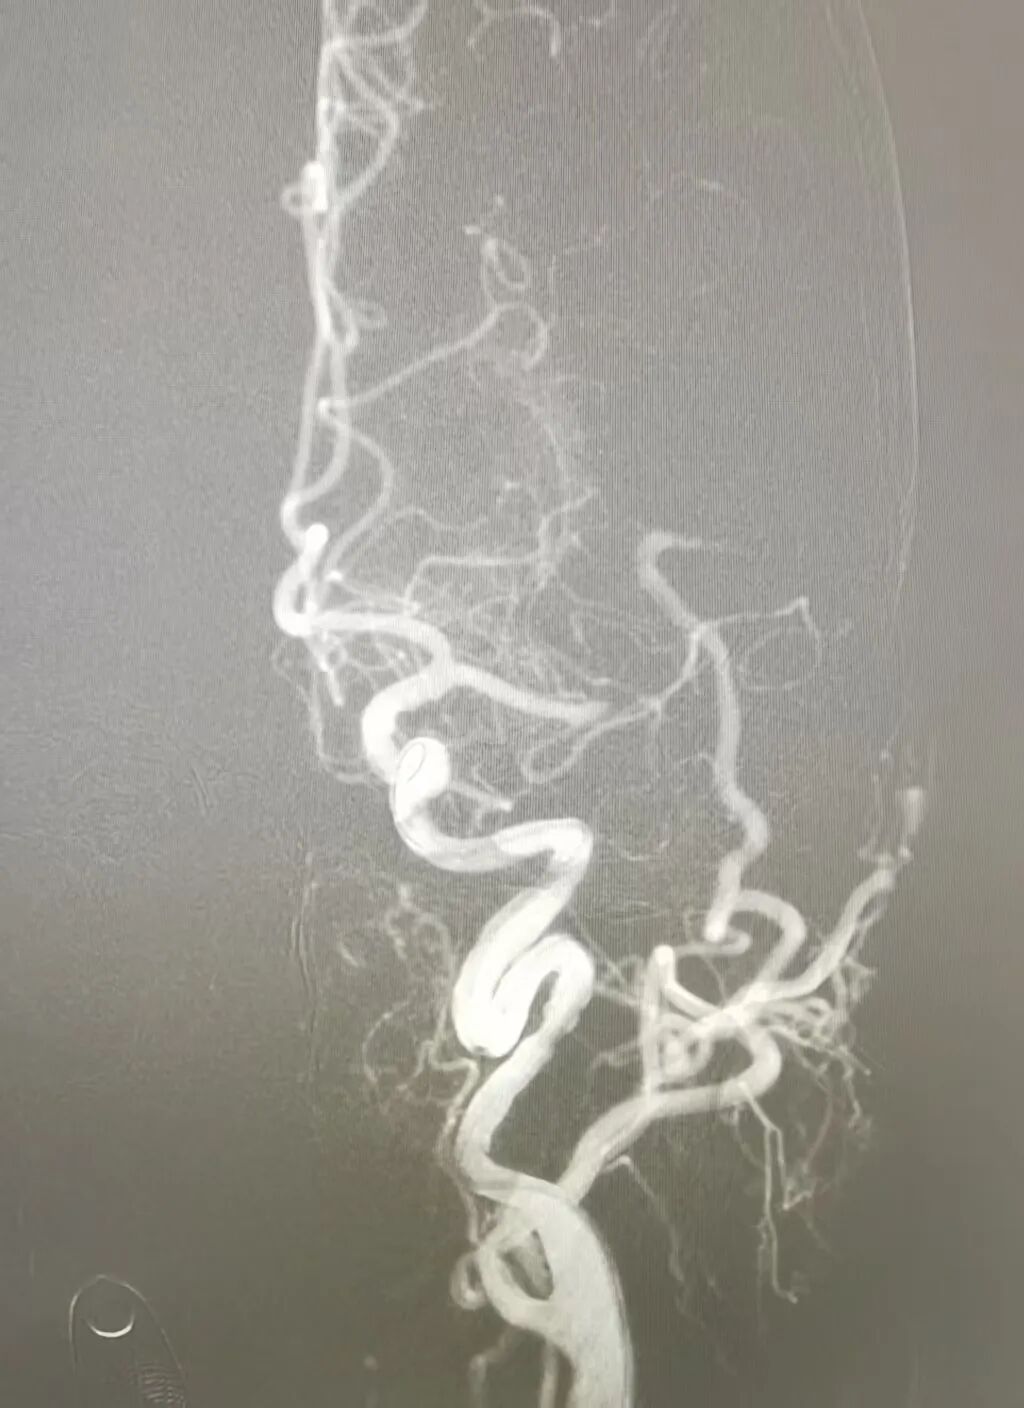

左侧大脑中动脉闭塞

关键时刻,卒中中心团队快速评估:余大伯虽然无法溶栓,但其发病时间短、大血管闭塞明确,且经CTP评估存在可挽救的“缺血半暗带”(即未完全坏死的脑组织),符合动脉取栓条件。经过与家属沟通,余大伯被火速转运至导管室。两小时后,血栓成功取出,血管再通;次日,他奇迹般苏醒,左侧肢体可抬,语言功能恢复,思维清晰。经后期规范治疗,余大伯出院时康复良好。这场与时间的赛跑,因动脉取栓技术的及时介入,画上了圆满的句号。

闭塞动脉成功开通